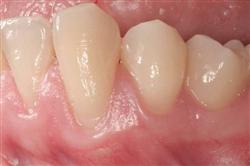

Cosmetic Soft Tissue Grafting

In addition to the functional problems previously mentioned, receding gums can look unsightly.

Longer looking teeth and exposed tooth roots give an "old" appearance to your smile. Some people cover their mouths when they smile for this very reason.

Cosmetic Soft Tissue Grafting can add a new youthful appearance to your smile. In your initial consultation with Dr. Hoidal, he will thoroughly explain what can be achieved in your particular case.